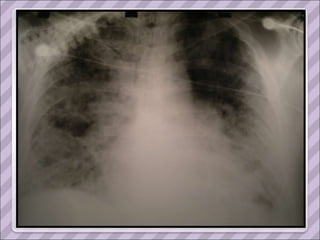

INGRESO 03/11

APP Sarcoidosis torácica  (1993, dx por biopsia ganglionar del mediastino. Estadio II) Compromiso cutáneo (eritema nodoso recurrente y refractario en MMII), ocular (uveítis) y del SNP ( mononeuropatía múltiple). Tratamiento prolongado con corticoides y azatioprina.  Cushing exógeno Diabetes inducida por esteroides Serología positiva para Hepatitis C en 2006